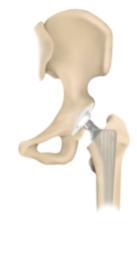

Bei den totalen Hüftendoprothesen (Hüft-TEP) werden in der Regel eine künstliche Hüftpfanne und eine Schaftprothese mit Aufsteckkopf implantiert. Hierfür stehen unterschiedliche Prothesenmodelle und Verankerungsmöglichkeiten (zementiert, zementfrei) zur Verfügung. Eine neuere operative Versorgungsmöglichkeit stellt der Hüftoberflächenersatz dar. Es handelt sich hierbei um ein besonders knochensparendes Prothesensystem, dessen klinischer Einsatz jedoch noch jung ist, sodaß potentielle Vorteile noch nicht abschließend beurteilt werden können.

Bei der zementfreien Hüftprothese besteht die Schaftprothese aus einer speziellen Titanschmiedelegieung, welche das Anwachsen von Knochen fördert. Den Gelenkpartner zur künstlichen Hüftpfanne bildet ein Aufsteckkopf aus Keramik.

Als

Pfannenersatz wird in das zuvor aufbereitete Pfannenlager eine

subhemisphärische Titanschale eingepresst oder geschraubt, in welche

dann spezielle Polyethylen- oder Keramik-Inlays eingebracht werden.